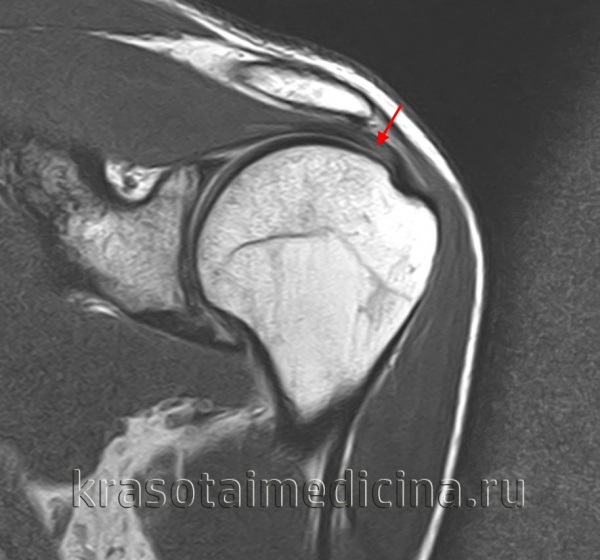

Диагноз повреждения ахиллова сухожилия выставляется на основании клинических данных, при необходимости может использоваться МРТ. В первые двое суток при незначительном расхождении концов сухожилия возможно консервативное лечение. На конечность накладывают гипс в положении максимального подошвенного сгибания сроком на 6 недель. При застарелых повреждениях и неудаче консервативной терапии показана операция.

Для уточнения диагноза используется сравнительная рентгенография коленных суставов (надколенник с больной стороны смещен кверху), МРТ коленного сустава и УЗИ сустава. Лечение оперативное, осуществляется в стационарных условиях. Колено разгибают, концы связки сближают и соединяют при помощи матрацных швов. При отрыве костной пластинки накладывают трансоссальные швы. Иммобилизацию продолжают 2-3 недели. После операции назначают антибиотики и анальгетики, в последующем – ЛФК, ультразвук, диадинамические токи, парафин и массаж.